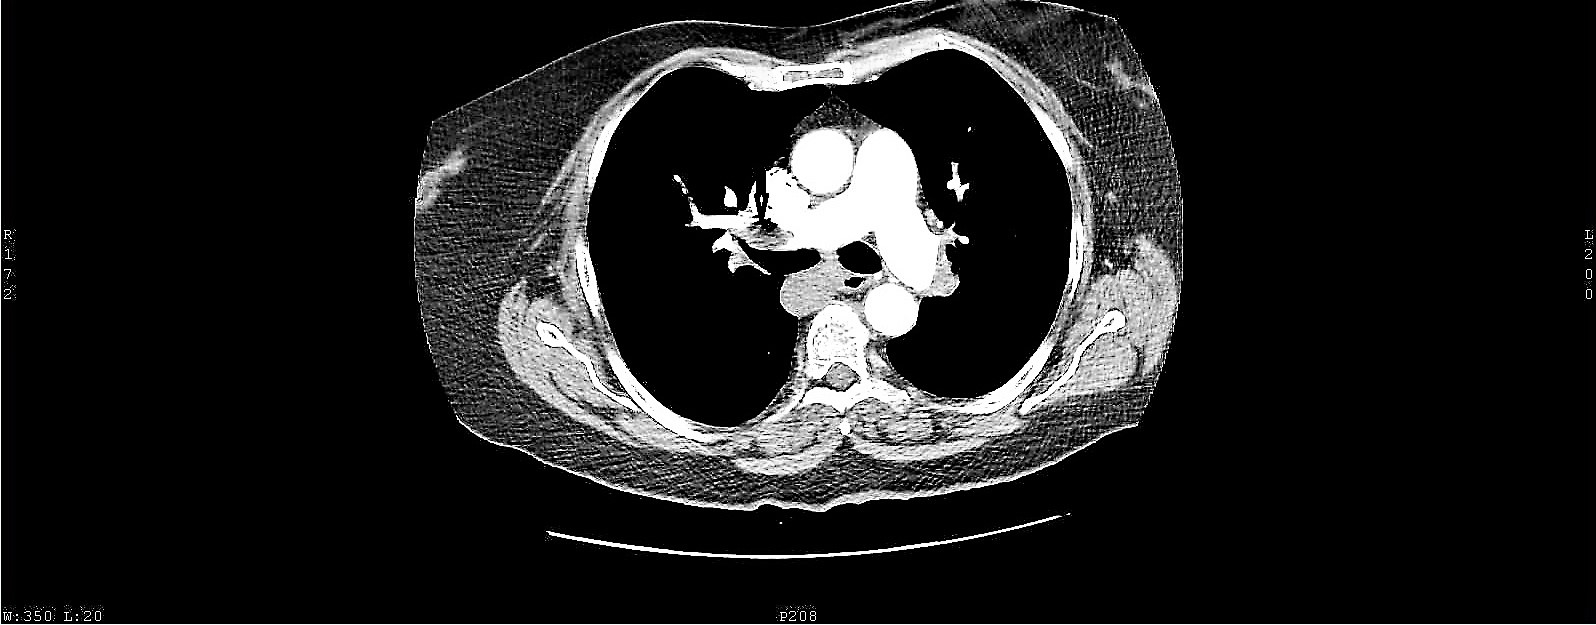

Paradoxical embolism is an uncommon cause of arterial occlusion with a high mortality burden. Current evidence suggests that patent foramen ovale is the most important etiological factor of paradoxical embolism, by acting as a pathway for a thromboembolic material originating from the peripheral veins, passing through the lungs and entering the systemic circulation. Here we present a case of paradoxical embolism in the mesenteric and renal arteries associated with pulmonary embolism and deep vein thrombosis in an elderly woman with no predisposing risk factor. A diagnosis of paradoxical embolism was considered and the presence of a patent foramen ovale was consequently confirmed with a transesophageal echocardiography. Urgent thrombolysis saved the life of the patient. Paradoxical embolism represents an emergency and therefore prompt diagnosis and initiation of therapy may prevent adverse outcomes.